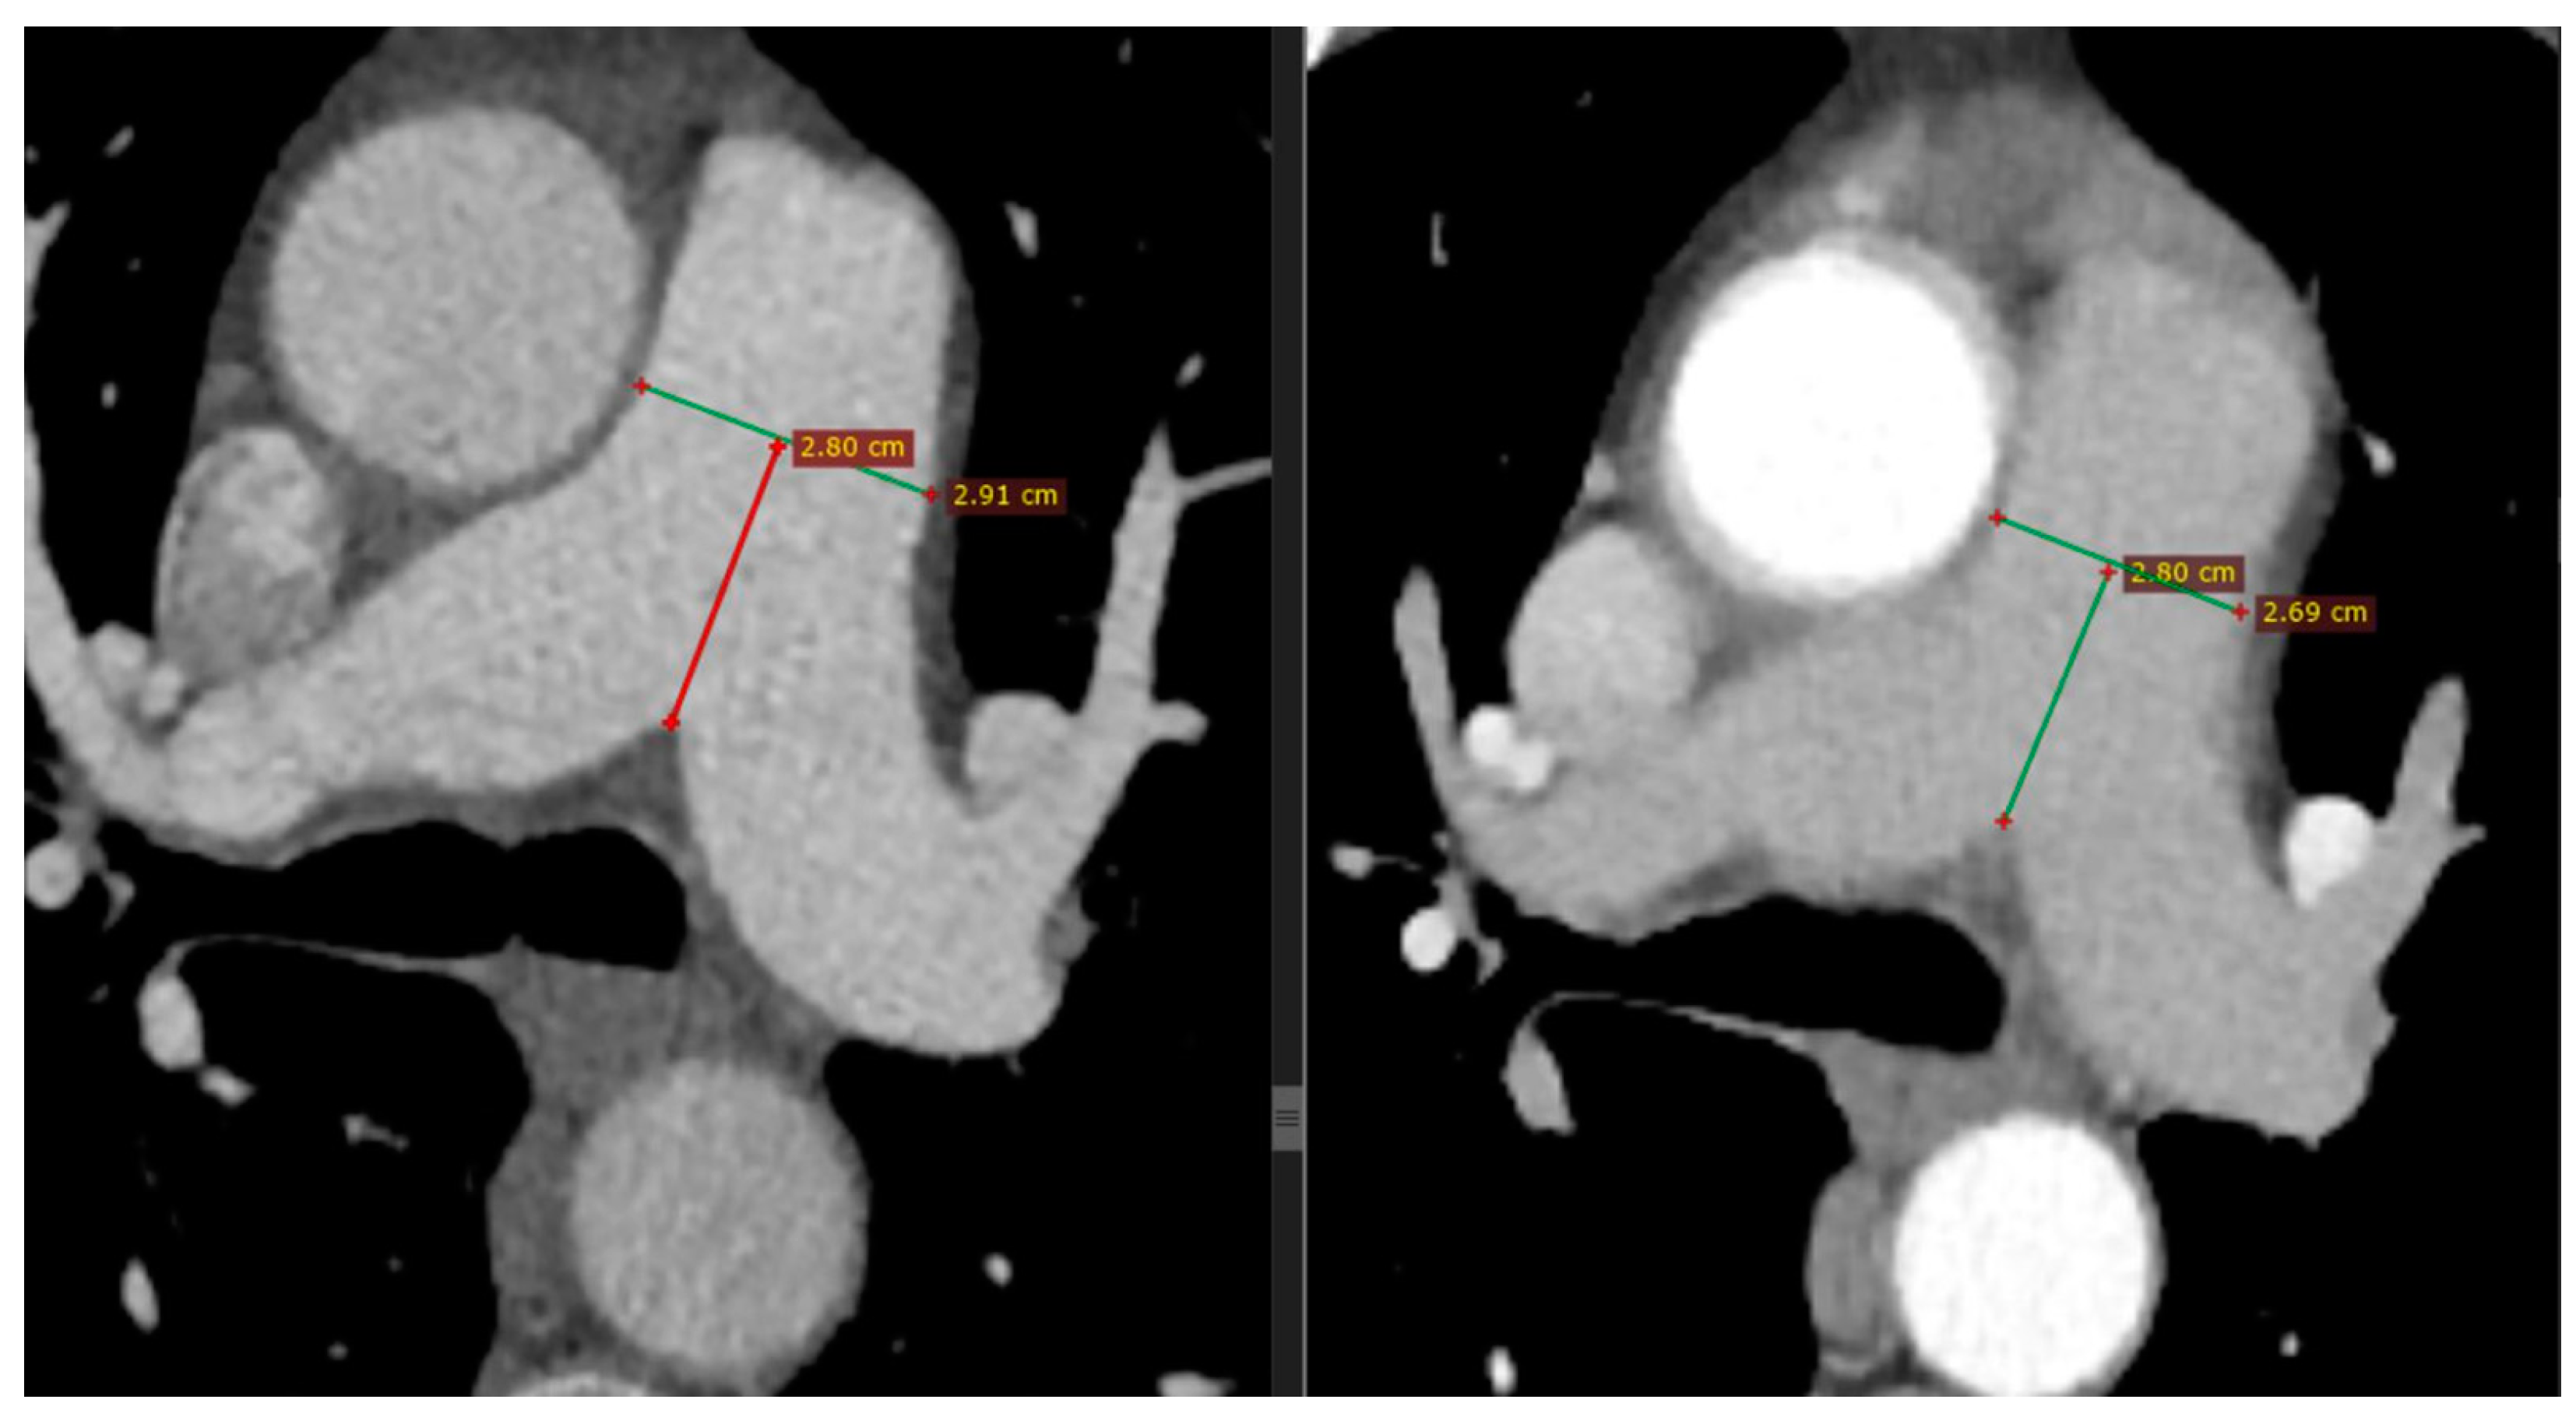

All patients intravenously received iodinised contrast agent following the CT pulmonary angiography (CTPA) protocol. The CT images were interpreted by two specialised radiologists who had extensive experience in chest imaging and were blinded to the clinical background of the patients. The metrics of the PA were extracted and the lung parenchymal findings were described, both in the acute phase of the infection and after the remission of the disease. The main PA diameter (MPAD) was measured at the level of the PA bifurcation at the level of the mid-aortic arch and the main carina (Figure 2); it was then classified according to the four-tier severity classification system of PA metrics on CT for the diagnosis and prognosis of PH, as previously described: normal if <2.7 cm for females or <2.9 cm for males, mild if ≥2.7 cm and <3.1 cm for females or ≥2.9 cm and <3.1 cm for males, moderate if ≥3.1 cm and <3.4 cm for both genders, and severe if ≥3.4 cm for both genders [18].

Figure 2. Representative chest CT images. Consecutive measurements of MPAD at mid-PA at the level of the mid-aortic arch and main carina on chest CT in a patient with COVID-19 pneumonia (left) and after 6 months (right), with a substantial decrease noted (from 2.91 to 2.69 cm). Horizontal green lines represent the MPAD, whereas vertical red and green lines represent the distance of MPAD from the bifurcation of the pulmonary artery.